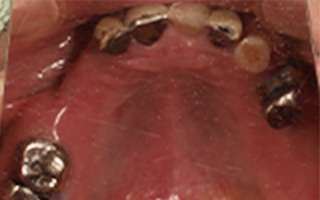

Before

After

| 55歳 男性 | |

|---|---|

| 主訴 | 前歯でしか咬めなく、食事を摂るのに非常に困難で辛い |

| 処置内容 | 上顎6本、下顎3本 |

| 治療費用 | 上顎: 約230万(税込) 下顎: 約120万(税込) |

| 治療期間 | 上顎: 1年(仮歯まで8ヶ月) 下顎: 8ヶ月(仮歯まで5ヶ月) |

| リスク | 上部構造物、仮歯の破折、術後の腫れ(3日)、人工歯根脱落リスクがあります |